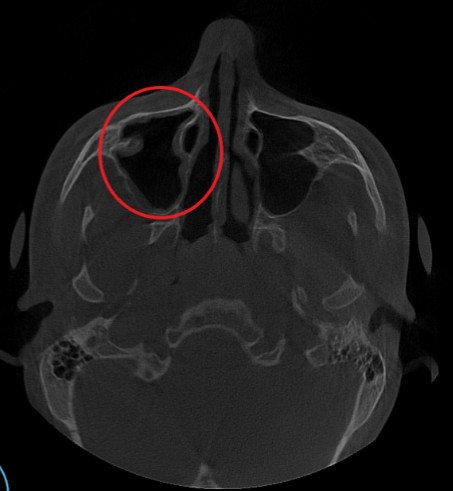

Проведена компьютерная томография околоносовых пазух, которая подтвердила наличие правостороннего гемисинусита (воспаление нескольких пазух с одной стороны), как следствие периодонтита зуба 1.6.

Представлено КЛКТ околоносовых пазух до начала лечения. Выделена зона воспаления пазух.

На снимке детально представлена область пораженного зуба 1.6.